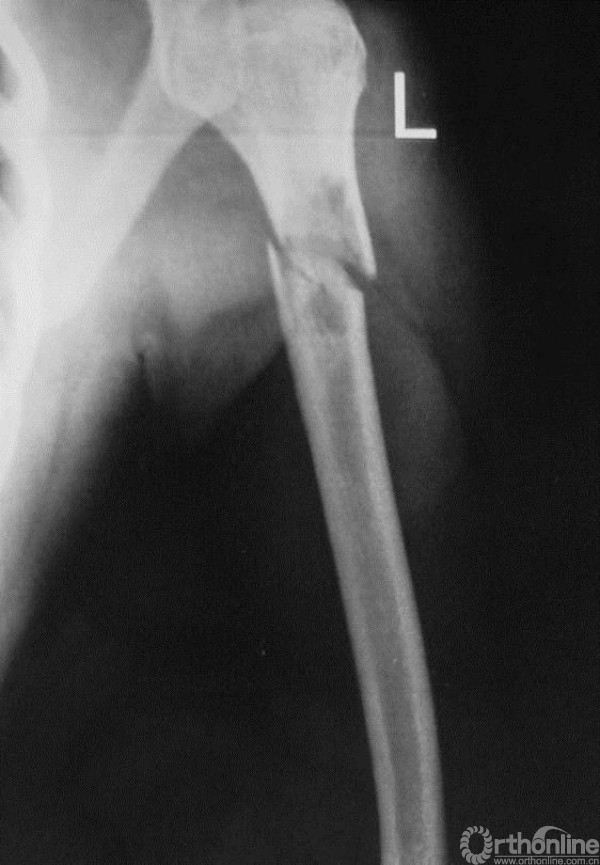

图13-1 病例一伤后X线平片正位

病例一:X线平片见病变内基质不均匀呈虫噬样破坏,边界不清楚,皮质骨受侵破坏。提示疾病具有一定的侵袭性表现。